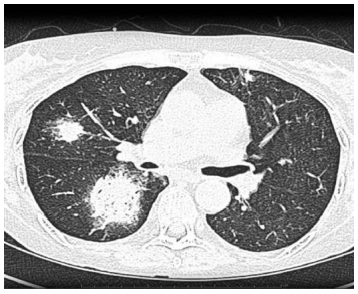

Um paciente masculino de 56 anos de idade, com leucemia mieloide aguda em quimioterapia, tem apresentado febre persistente há 5 dias, juntamente com tosse seca e dispneia. Esses são sintomas refratários ao uso de meropenem e vancomicina prescritos pela equipe de hematologia do serviço médico. O paciente apresentou-se eupneico em ar ambiente, normotenso, normocárdico, bem-perfundido e sem alteração neurológica. Foi realizada uma TC de tórax, que está disposta a seguir.